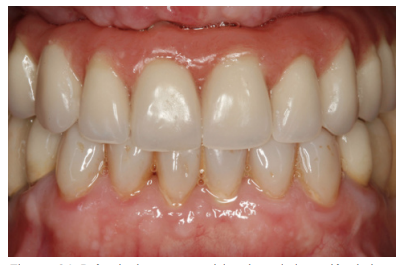

Cuatro meses después de la cirugía inicial de regeneración del maxilar se lleva a cabo un nuevo Cone-beam dental, en el que se planifica la siguiente fase de la cirugía en función de la ganancia ósea que se ha logrado con los injertos en bloque y la técnica de Split en dos fases. En las imágenes podemos observar como en las zonas de máxima atrofia, donde se colocan los bloques se ha logrado una anchura que triplica la inicial (Figuras 19 y 20). En la apertura del colgajo se observa como las imágenes del TAC de planificación se corresponden con la realidad, y además que la zona tratada mediante Split en dos fases ha logrado también una anchura de cresta que ahora permite la retirada de los implantes transicionales y la inserción de nuevos implantes en esta posición, con una mejor situación de partida y eje para la confección posterior de la prótesis (Figuras 21-22). Se procede a la inserción de los implantes y se realiza una prótesis provisional de carga progresiva apoyada en los implantes colocados en la primera fase quirúrgica. De este modo, la paciente puede tener una prótesis fija sobre implantes que servirá para ir dando forma a los provisionales en cuanto a estética y función de cara a la prótesis definitiva (Figuras 23-24).

Cuatro meses después se procede a la carga de los implantes insertados en esta segunda fase quirúrgica. De nuevo se opta por unas segundas prótesis provisionales de carga progresiva, elaboradas del mismo modo que las anteriores Tres meses después la oclusión está preparada para la confección de la prótesis definitiva, por lo que se transforma la prótesis en una prótesis metal-cerámica, atornillada sobre transepitelial confeccionada mediante cad-cam (Figuras 25-26). La paciente ha recuperado la función demandada, así como la corrección de la oclusión de la prótesis completa, que presentaba una mordida cruzada lateral derecha con disminución de la dimensión vertical al inicio del tratamiento. La paciente acude a sus revisiones y el tratamiento se mantiene estable tal como se muestra en las imágenes tomadas a los 10 años de seguimiento (Figuras 27-28).